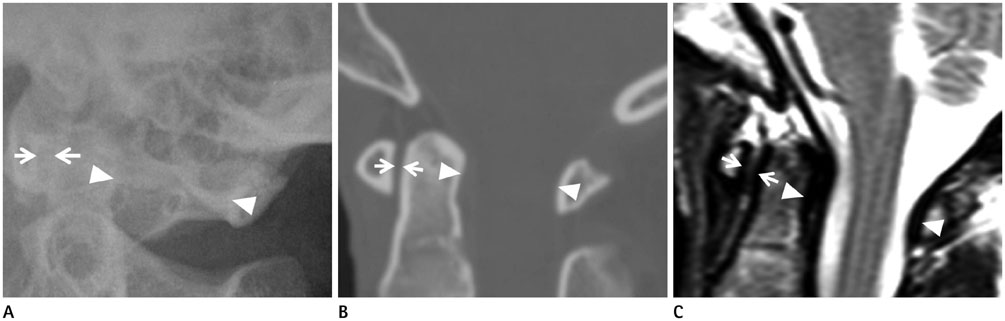

To determine the normal values of the anterior atlantodental interval (AADI) and posterior atlantodental interval (PADI) on plain radiography, multidetector CT (MDCT) and MRI, as well as the dural sac width and spinal cord diameter at the atlantoaxial joint level on MRI.

In total, 60 subjects underwent plain radiography, MRI and MDCT. We obtained values for AADI and PADI on plain radiography, MDCT, and MRI, and for dural sac width and spinal cord diameter on MRI. Two radiologists independently measured each value and a consensus was reached.

The average AADI was 1.5 +/- 0.5 mm on plain radiography, 1.4 +/- 0.3 mm on MDCT, and 1.6 +/- 0.5 mm on MRI. The average PADI was 20.6 +/- 2.4 mm on plain radiography, 18.0 +/- 2.1 mm on MDCT, and 17.7 +/- 1.9 mm on MRI. The dural sac width was 13.7 +/- 1.8 mm, and the spinal cord diameter was 7.8 +/- 0.7 mm. Interobserver agreement was 0.701-0.927 and intraobserver agreement was 0.681-0.937.